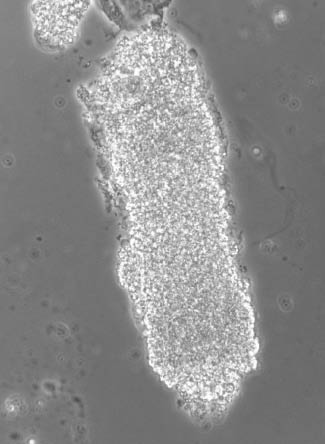

Granular casts

These casts have a surface composed of granules, which can vary in size (Figure 1). The granules can be rather heterogeneous, ranging from fine (finely granular cast) up to coarse (coarsely granular cast), dark, clear, and pigmented. It has been demonstrated that in patients with proteinuria, fine granules contain ultrafiltered proteins which have been reabsorbed by tubular cells [17], whilst in non-proteinuric patients coarse granules probably derive from the degeneration of cellular elements, such as leukocytes and renal epithelial cells present in the tubular lumen during cast formation [18]. The presence of granular casts always reflects renal injury, and recent studies on patients with acute kidney injury have demonstrated that they are, together with renal tubular epithelial cells (RTEC) and RTEC-containing casts, a sensitive marker of acute tubular necrosis [19–21].

A finely granular cast (phase contrast microscope, original magnification 400×).

By courtesy of Dr. G.B. Fogazzi.